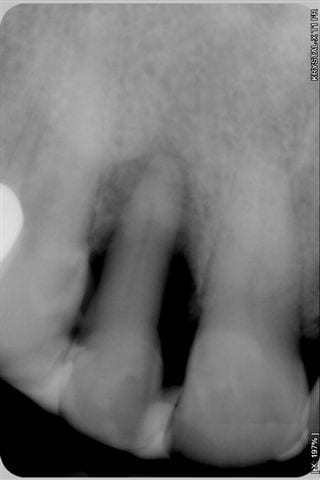

Souvenez vous, il y a 6 mois, je vous ai posté des photos sur un cas de parodontopathie aiguë localisée à la 12, voici les photos et radio 6 mois plus tard, après traitement de la paro au laser diode 980 nm sous bipivone puis H2O2, bio stimulation tous les 15 jours et reconstruction de la couronne en emax avec le CEREC 6 mois plus tard.

Oui, belle gencive, collets toujours alignés et effectivement la couronne est bien maquillée.

Résultat clinique et radiologique plutôt encourageant à 6 mois.

- Dommage que les radios ne soient pas indexées avec leur date, car avec le désordre dans lequel le serveur les met, c'est un peu plus difficile de suivre l'évolution de la guérison (qui n'est pas encore complète apparemment).